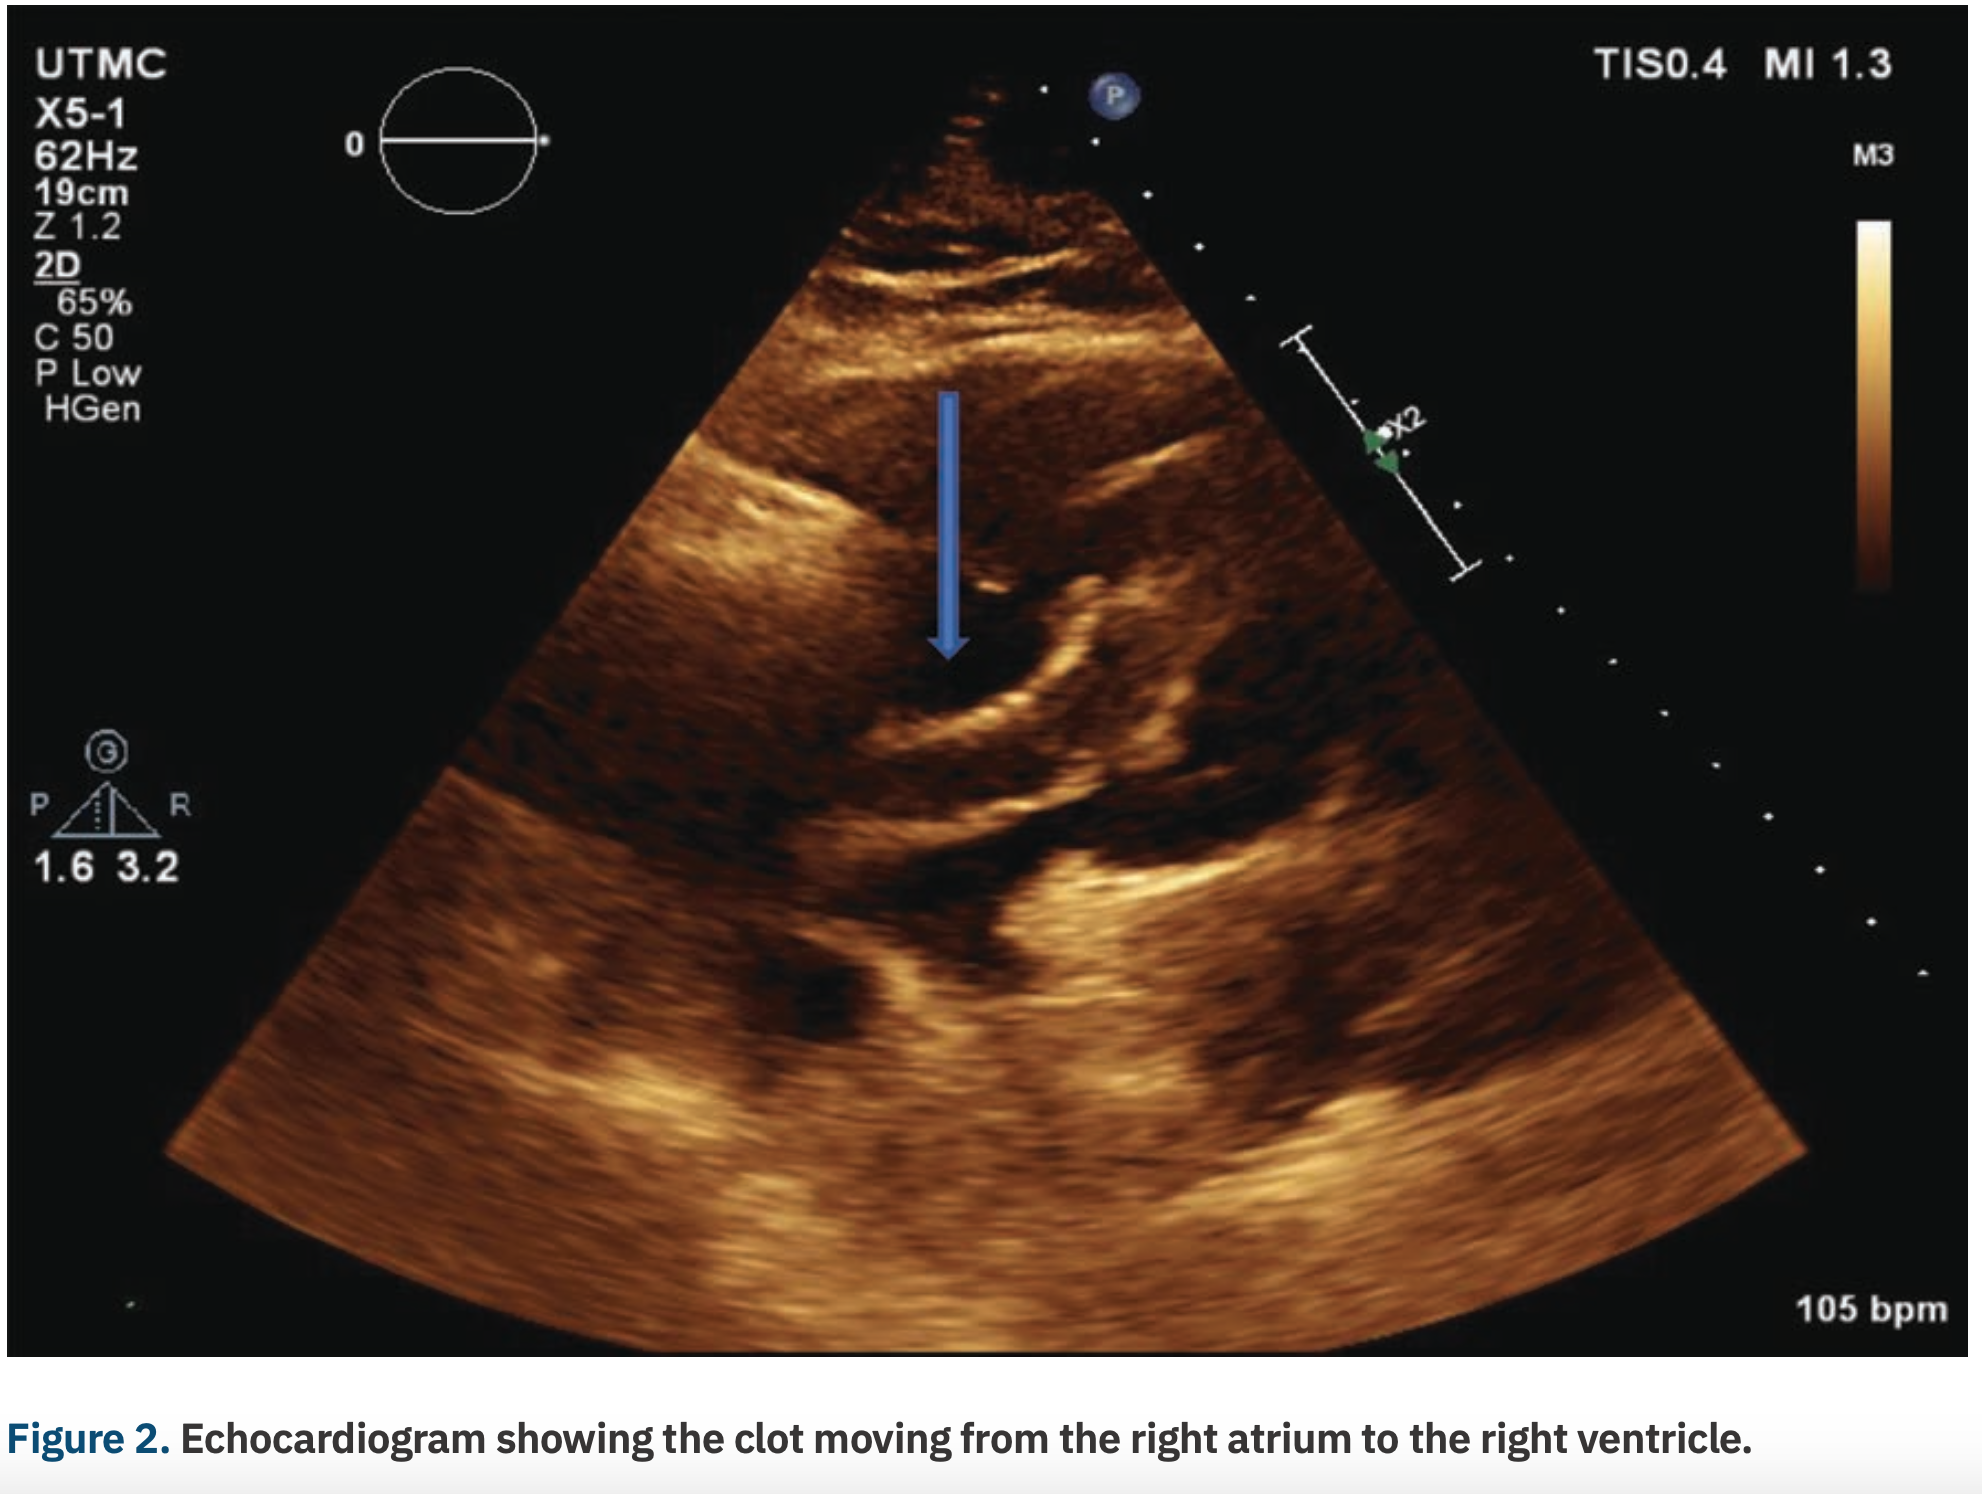

An 80-year-old male with no known past medical history presented to the emergency department at an outside facility with increasing dyspnea for the past ten days. Two weeks prior to his presentation, the patient had a fall. The patient had been immobile since then. Computed tomography (CT) angiogram of the chest showed a completely occluded right pulmonary artery and a partially occluded left pulmonary artery (Figure 1). Duplex of the lower extremity also revealed thrombosis of the left common femoral vein, femoropopliteal, and tibioperoneal veins. His BNP was also noted to be elevated at 306 pg/ml and his troponins were also elevated at 0.09 ng/ml (upper limit was 0.04 ng/ml). As he was hemodynamically stable, the patient was transferred to our facility for possible catheter-directed thrombolysis given his clinical picture of submassive pulmonary embolism. On arrival, an emergent bedside echocardiogram showed a clot in transit from the right atrium to the right ventricle (Figure 2), as well as a severely enlarged right ventricle and moderate tricuspid regurgitation. Due to the huge clot burden, right ventricular strain, and clot in transit, the patient underwent emergent surgical embolectomy. Surgery was successful in removing most of the clot with no complications. Intraoperatively, the clot was found to extend from the right atrium through the tricuspid valve into the right ventricle and all the way to the main pulmonary arteries. There was some residual thrombus in subsegmental areas that was left for medical treatment. The patient had remarkable improvement and was able to go home in a couple of days. He was discharged on rivaroxaban. On follow-up, the patient elected to have an inferior vena cava (IVC) filter placed, which was done successfully. Repeat CT angiography was done 4 months after presentation and showed resolution of the remaining thrombi. The patient continues to do clinically well on outpatient follow-up.

Echocardiography remains the gold standard for risk stratification of pulmonary embolism as well as for making the diagnosis of intracardiac thrombi, with the added benefit of obtaining an idea of the clot origin. Morphologically, the right heart clots can be divided into two types, A and B. Type A clots have a worm-like shape, are very mobile, and usually represent peripheral venous clots that lodge temporarily into the right heart. Type B, on the other hand, are similar in shape to the left heart thrombi, less mobile, attach to the right atrial or ventricular wall, and have broad-based attachment, indicating that Type B clots develop within the right heart.7